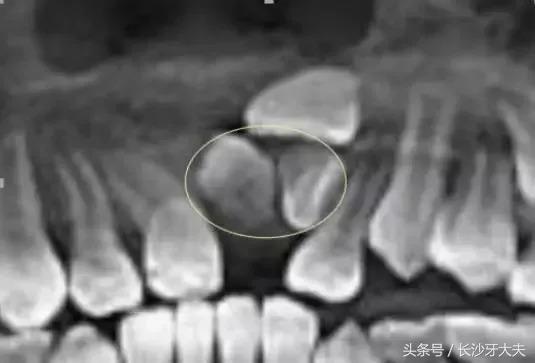

看完这些,大家对我有所了解了吧,正如上面所讲,如果是在替牙期,我的位置会阻碍正常新牙的萌出通道,导致对应恒牙的萌出位置发生异常,例如牙齿发生扭转、倾斜、拥挤或牙缝过大甚至不能萌出。

而且我奇怪的外形也会严重影响小主人的美观及心理健康;

也有少数情况下可能导致含牙囊肿的发生,若无视它继续生长,骨质逐渐向周围膨胀,则会形成面部畸形,根据不同部位可出现相应的局部症状。